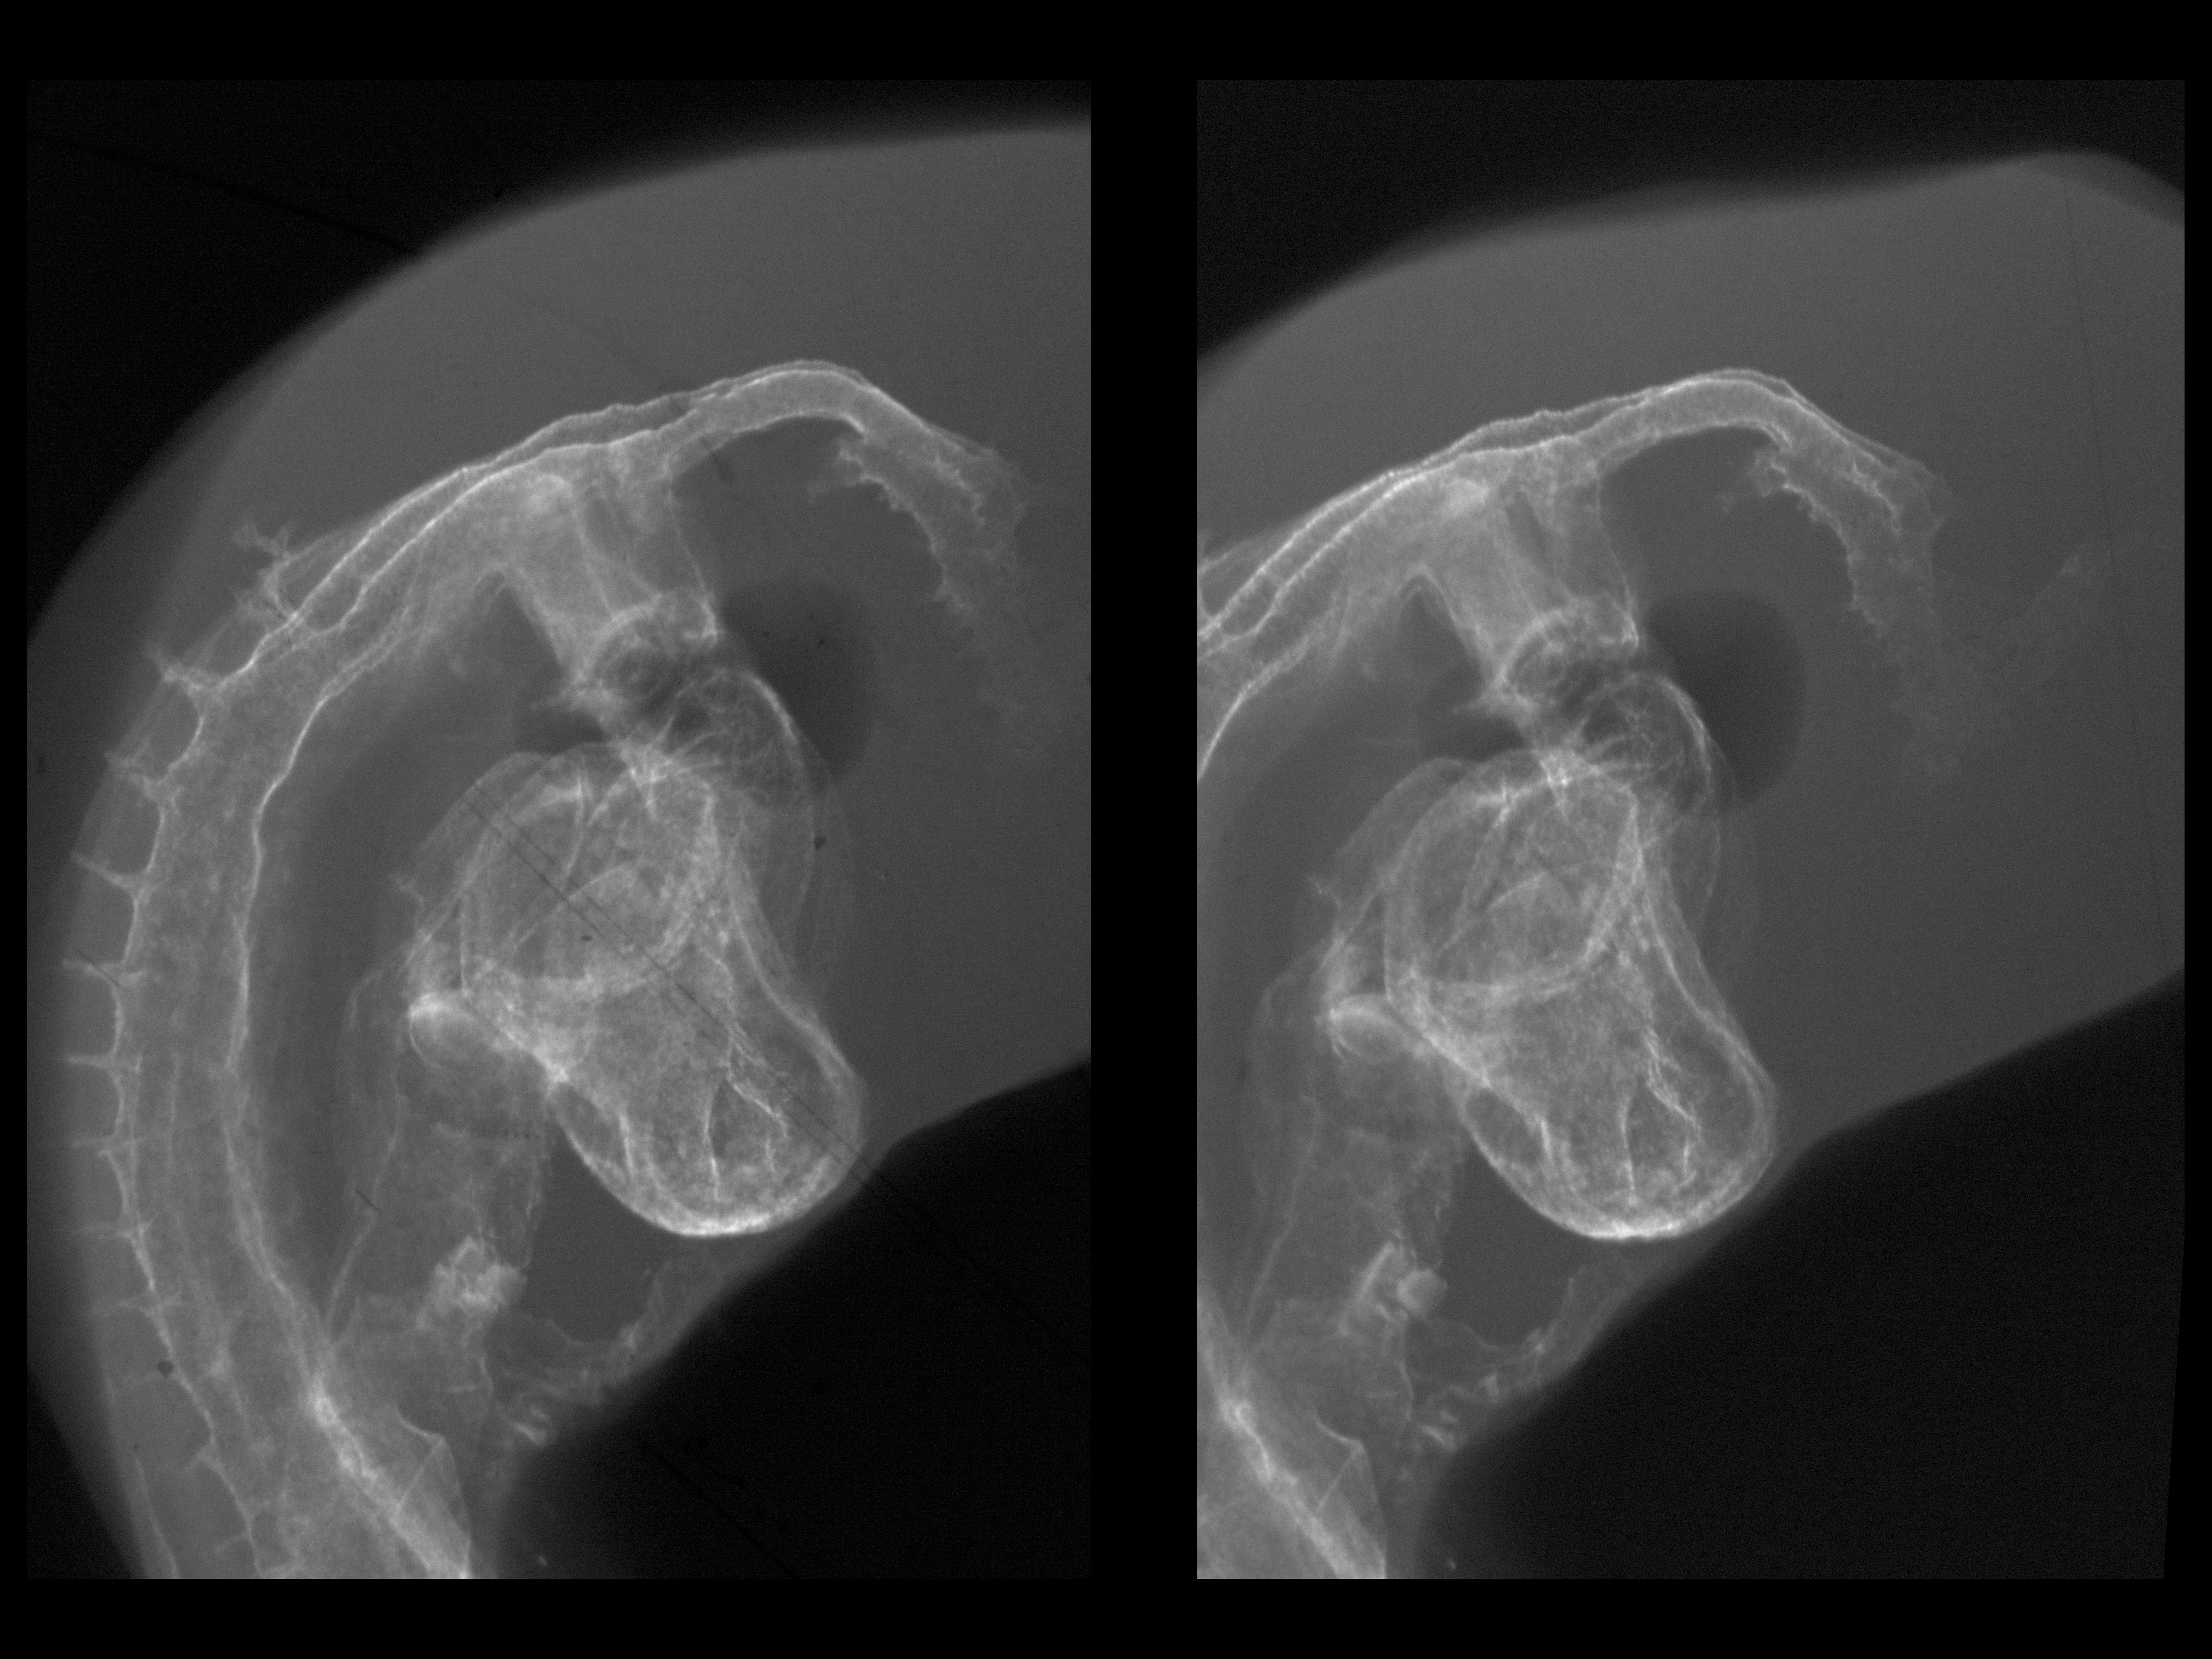

Chick Embryo Microangiography

Hamburger-Hamilton (HH) Stage 16 (approx. 2.1 - 2.5 days)

Stereo X-Ray Micrographs